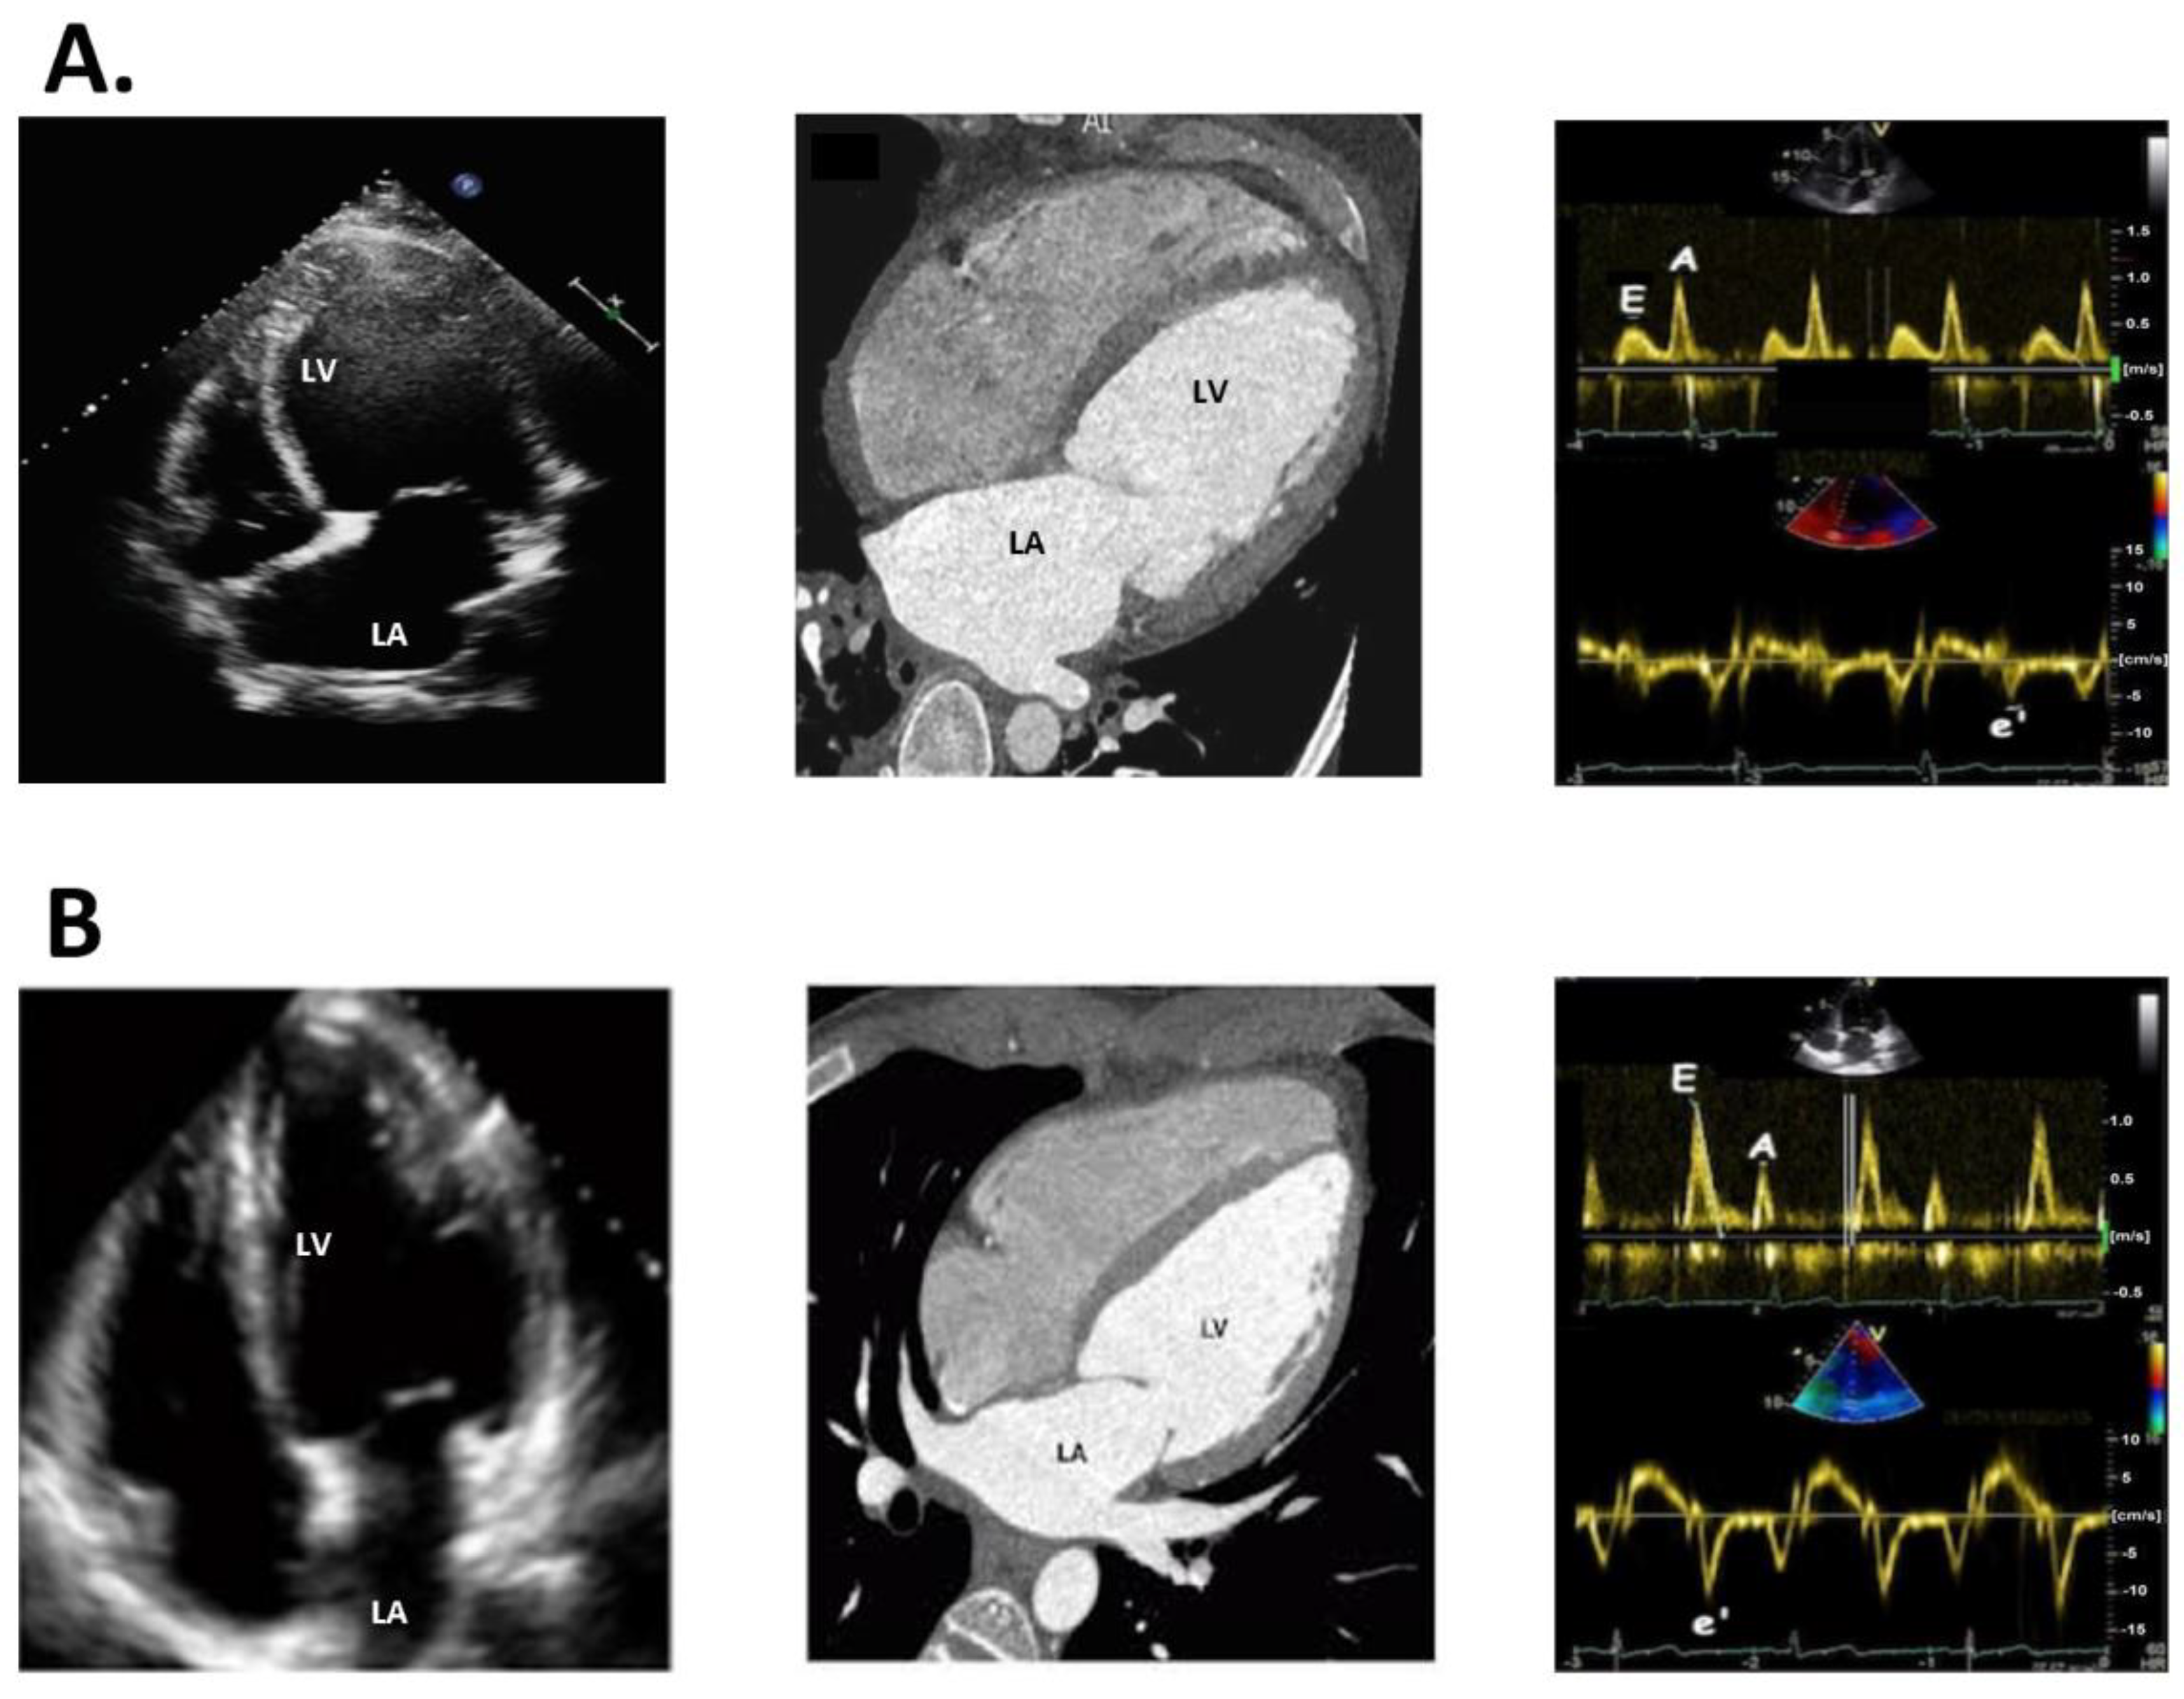

3.1. Echocardiography

3.2. Cardiac CT